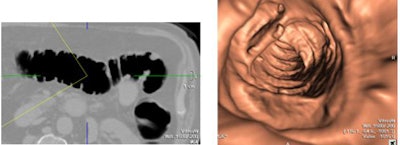

![]() |

| Inadequate bowel preparation at VC is especially problematic in elderly patients. All images courtesy of Patrick McLaughlin. |

"In our experience, these can be especially problematic in elderly patients. However, in day-to-day practice, side effects associated with mechanical bowel prep and incomplete bowel preparation may not be as obvious," McLaughlin said. "They include dehydration, renal function disturbances, and electrolyte disturbances, of which there have been case reports of fatalities."